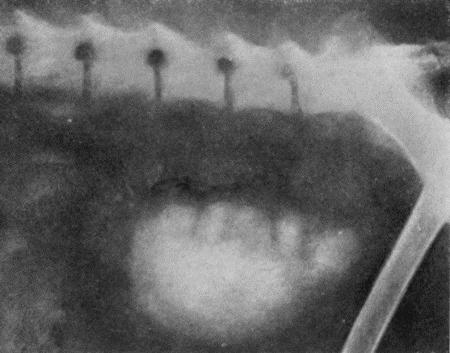

Камни мочевого пузыря и уретрального канала (calculi vesicales et urethrales). Мочевые камни встречаются чаще у собак старого возраста и наблюдаются, в основном, у самцов. Они состоят из карбоната кальция, мочекислого аммония, уратов, оксалатов, трипельфосфатов и цистина. В мочевом пузыре собак часто располагается несколько камней, которые в этих случаях на своих соприкасающихся поверхностях будут иметь фасетки (рис. 101). Встречаются камни и больших размеров, но чаще бывает песок.

При пальпации мочевого пузыря через брюшную стенку обнаруживают его переполненным мочой. Мочепузырные камни в этом случае можно не обнаружить. В затруднительных случаях прибегают к рештеноисследованию (рис. 103). Моча нередко содержит песчинки.